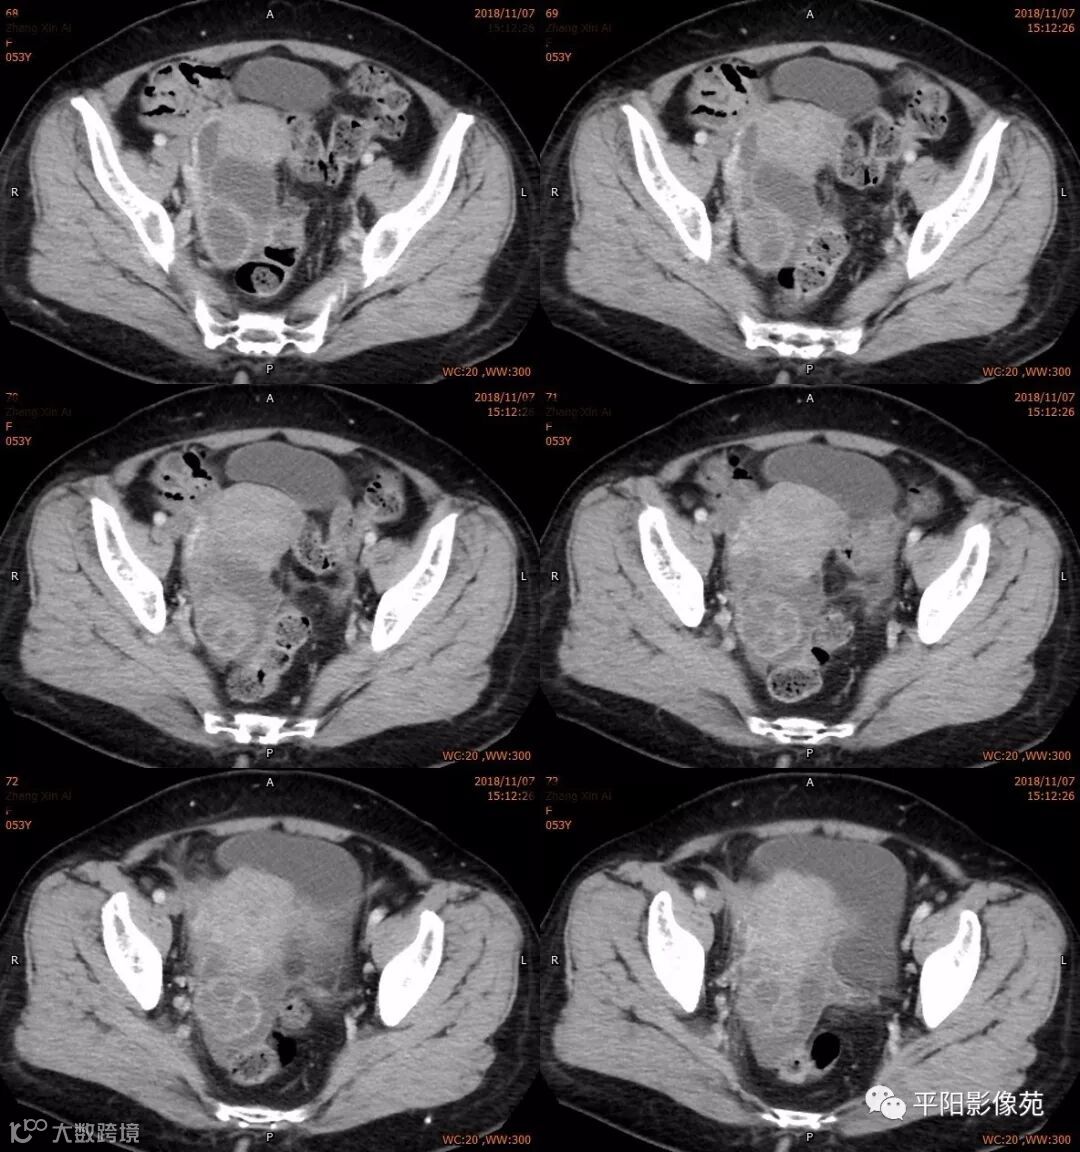

影像特点

右附件区薄壁囊性病变,壁明显强化,边界不清,供血动脉源自子宫动脉,且局部动脉血管增多;其内侧可见卵圆形无强化囊性病灶。

附件区病变多见于卵巢,以囊性为主的病灶多为卵巢囊肿、粘液/浆液性囊腺瘤、皮样囊肿等,这些病灶都具有鲜明瘤体结构,且壁强化多为轻-中度,供血动脉多源自卵巢动脉;而本例患者右附件区薄壁囊性病灶,多位置观察形态为迂曲管状,且壁有明显延迟强化,供血动脉源自子宫动脉,较对侧血管丰富,故而考虑源自输卵管或子宫病变,但子宫发生的薄壁囊性病变较少,多见于子宫肌瘤囊变,完全囊变者少见,且形态轮廓与肌瘤相同为球形故而排除,结合患者腹痛前有感冒病史,且有压痛,因此考虑输卵管积脓可能。其内侧无强化囊性肿块,考虑卵巢囊肿可能。